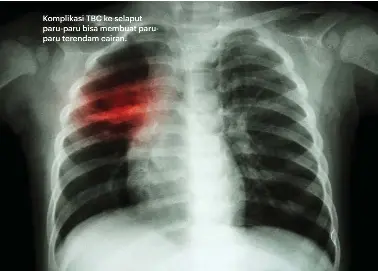

Sering Dianggap Sama, Ini Beda Gejala Kanker Paru dengan TBC Halaman all - Kompas.com Perencanaan Global Diharapkan Akhiri Epidemi TBC pada 2030 APA ITU TB PARU? – Rumah Sakit Kasih Ibu Surakarta Flek Paru-Paru Penyakit Berbahaya yang Bisa Disembuhkan Awas, Tuberkulosis Bisa Bikin Pasien Hidup dengan 1 Paru-Paru - Gaya Tempo.co Apa Penyebab Flek Paru-Paru? Cek di Sini Bakteri TB Ditemukan pada Pasien yang Sudah Sembuh Ternyata 9 Bulan Makan Obat Anti Tuberkulosis Itu Tidak Sia-sia - Kompasiana.com Ternyata 9 Bulan Makan Obat Anti Tuberkulosis Itu Tidak Sia-sia - Kompasiana.com Selain Rokok, Ini 5 Penyebab Flek pada Paru-Paru Batuk Kanker Paru Tidak Ada Bedanya dengan Batuk Biasa atau Batuk TBC - Pos Belitung Tuberkulosis (TBC) – BLUD RSU Kota Banjar Bukan Batuk Biasa, Waspadai TBC dengan 8 Gejala Khasnya - Health Liputan6.com Penyakit Tuberkulosis Dapat Disembuhkan - RS Awal Bros Kab Bandung Endemis TBC | BaleBandung Pekanbaru Temukan 3.700 Kasus TB Paru | Republika Online Sering Salah Diagnosa, Dikira Cuma Kena TBC Ternyata Ada Kanker Paru - Warta Kota Pneumonia Vs TBC, Sama Nggak Sih? Yuk Tanya Dokter Paru TB Paru yang Diabaikan Bisa Menjadi TB Tulang? Flek Paru : TB or not TB? - Kompasiana.com Gejala TBC (Tuberkulosis), Penyebab, Biaya Berobat & Dokter - Smarter Health TBC, Penyakit Menular Penyebab Kematian No 1 di Dunia – TROPMED UGM Peneliti Temukan Cara Baru Deteksi Penyakit TB Demam dan Berat Badan Turun, Bisa Jadi Gejala Penyakit TBC - Halaman all - Tribun Bali Foto Rontgen, Ini yang Harus Anda Ketahui - Alodokter Rumah Sakit Jiwa Prof. Dr. Soerojo Magelang: STOP Rantai Penyebaran Tuberculosis Tak Hanya Paru-paru, 5 Organ Ini Juga Diserang Kuman TB Inna Riana: Sembuh dari TBC? Tentu Bisa! Diagnosis Tuberkulosis Paru - Alomedika Obat TBC Paru Kronis Yang Ampuh Dan Tanpa Efek Samping - kumparan.com TBC.mp4 - YouTube Puluhan Ribu Pasien TBC Putus Obat karena Pandemi Covid-19 Seorang Guru Ngaku Derita TBC demi Libur Panjang, Dampaknya Tak Terkira - Tribun Manado Mitos dan Fakta Seputar TBC Serta Bagaimana Pengobatannya - Dokter Indonesia Tuberkulosis (TBC) – BLUD RSU Kota Banjar Hati-hati! TBC Menular | Indonesia Baik Kenali Penyakit TBC dan Tahapan Penularannya – Suara Surabaya Memutus Rantai Penyebaran Tuberkolusis - Lifestyle Bisnis.com Gejala TB Paru Ini Harus Diwaspadai, Termasuk Batuk Terus-menerus Berikut Nama Obat Herbal Alami Untuk Flek Paru Paru | Asma | Dan Batuk Menahun. | by OKE DE NATURE | Medium Kenali Ciri-ciri TBC Tulang dan Cara Mengobatinya - Halaman all - Tribun Manado Mengenal TBC, Penyakit yang Diduga Menyerang Suami Soraya Haque Halaman all - Kompas.com Apa yang dimaksud dengan Tuberkulosis Paru ? - Ilmu Kedokteran - Dictio Community Penderita TBC Miliki Risiko Kanker Paru-paru 2 Miliar Orang di Dunia Kena TBC - Health Liputan6.com Tak Hanya Paru TBC Juga Bisa Menyerang Bagian Tubuh Ini 7 Ciri-ciri Paru-paru Basah dan Sederet Penyakit di Baliknya Kenapa Penderita TB Juga Mengidap Diabetes Mellitus - Health Liputan6.com TBC PARU-PARU | RADANG PARU-PARU | BRONCHITIS | Breakthrough Generation Perhimpunan Dokter Paru Indonesia Klik paru: TB PARU, jenis TB yang paling sering Apa Sih Bedanya Paru-paru Basah dan TBC? Mengenal Tuberculosis Alias TBC, Gejala, dan Pencegahannya - Tirto.ID Perlu Banget Memahami Penyakit Tuberculosis Paru (TBC Paru) | KASKUS Flek Paru : TB or not TB? - Kompasiana.com TBC Usus, Infeksi Bakteri Tuberkulosis yang Menyerang Organ Perut Masalah Kesehatan Serius Yang Ditimbulkan Penyakit Tb Paru Dari Minim Gejala Sampai Meradang, Ini Gambar Paru-paru Pasien Corona Materi] Penyakit pada Sistem Pernapasan Manusia ~ ROFA Education Centre Wah, Ternyata ‘Flek’ TBC di Paru-paru Kanan Saya Bisa Hilang, Dok Halaman all - Kompasiana.com Gejalanya Nyaris Sama, Ini Beda Bronkitis dan Penyakit Paru Lainnya Gambar Penyakit TBC (tuberculosis) | SEHAT.link Tuberculosis Interpretasi Rontgen Toraks - Alomedika Macam Penyakit Paru-Paru, Dilengkapi Gejala yang Perlu Diketahui - Health Liputan6.com Gejala, Penularan Dan Pencegahan Tuberculosis ( TBC ) - WinNetNews.com 7 Ciri-ciri Paru-paru Basah dan Sederet Penyakit di Baliknya Termasuk yang Paling Mudah Menular, Berikut Gejala TBC Menurut Dokter Spesialis Paru - Tribun Manado Detoksifikasi Paru Paru | Shopee Indonesia PressReader - Intisari: 2019-01-01 - Jangan Salah, Orang Gedongan Juga Bisa TBC! OBAT PENYAKIT TBC PARU Merokok, Paru Paru, Tbc gambar png MEMBACA KELAINAN PADA HASIL RADIOGRAFI PARU – Random Thoughts Rontgen Thorax: Fungsi, Proses, dan Kapan Harus Menjalaninya Cara Menyembuhkan Paru Paru Bolong | by Obat QnC Jelly gamat | Medium 10 Gejala Penyakit TBC dan Cara Pengobatannya, Kenali Sejak Dini Sebelum Terlambat - Health Liputan6.com 5 gambar obat paru paru yang sangat familier di masyarakat | by cinta kasih | Medium HIV Temenan Sama TB? | ODHA Berhak Sehat Fakta Penyakit TBC (Tuberkulosis) Yang Harus Diketahui Tbc Merk Obat paru paru bengkak akibat batuk kronis atau tbc menahun Bercak Paru pada Penderita TBC Apakah Bisa Hilang? Nurul ‘Ilmy Space: Waspada TBC Tak Hanya Paru-paru, TBC Juga Bisa Menyerang 6 Organ Tubuh Ini Ini Cara Orang Tua Dulu Mengobati Penyakit TBC - MerahPutih TBC (Tuberkulosis) - Gejala, penyebab dan mengobati - Alodokter TB Paru Bisa Sembuh, Baca Keterangannya! - bernas.id Pengalaman Saya dengan TBC Paru | KASKUS Apakah TBC Bisa Sembuh Total? Ini Kuncinya | Hello Sehat Apa yang dimaksud dengan Tuberkulosis (TBC) Paru pada Anak? - Ilmu Kedokteran - Dictio Community Cara menutupi flek paru-paru.agar lolos rotngen. | Trik unik Gambar Paru Pasien Corona Tunjukkan Betapa Bahayanya Covid-19 Gangguan pada Sistem Pernapasan Manusia dan Upaya untuk Mencegah atau Menanggulanginya - Buku Sekolah Extrapulmonary Tuberculosis Rumah Sakit Jiwa Prof. Dr. Soerojo Magelang: STOP Rantai Penyebaran Tuberculosis Paru-paru Terisi Cairan, Bisakah Disembuhkan? Penyebab TBC Penyakit Menular yang Mematikan, Kenali Sedini Mungkin Penyakit Paru Paru Kering | Paru-paru, Alam, Pemandangan OBAT TBC PARU-PARU HERBAL: Obat batuk berdarah berdarah atau tb paru paru Tbc, Hari TB Sedunia, Paru Paru gambar png